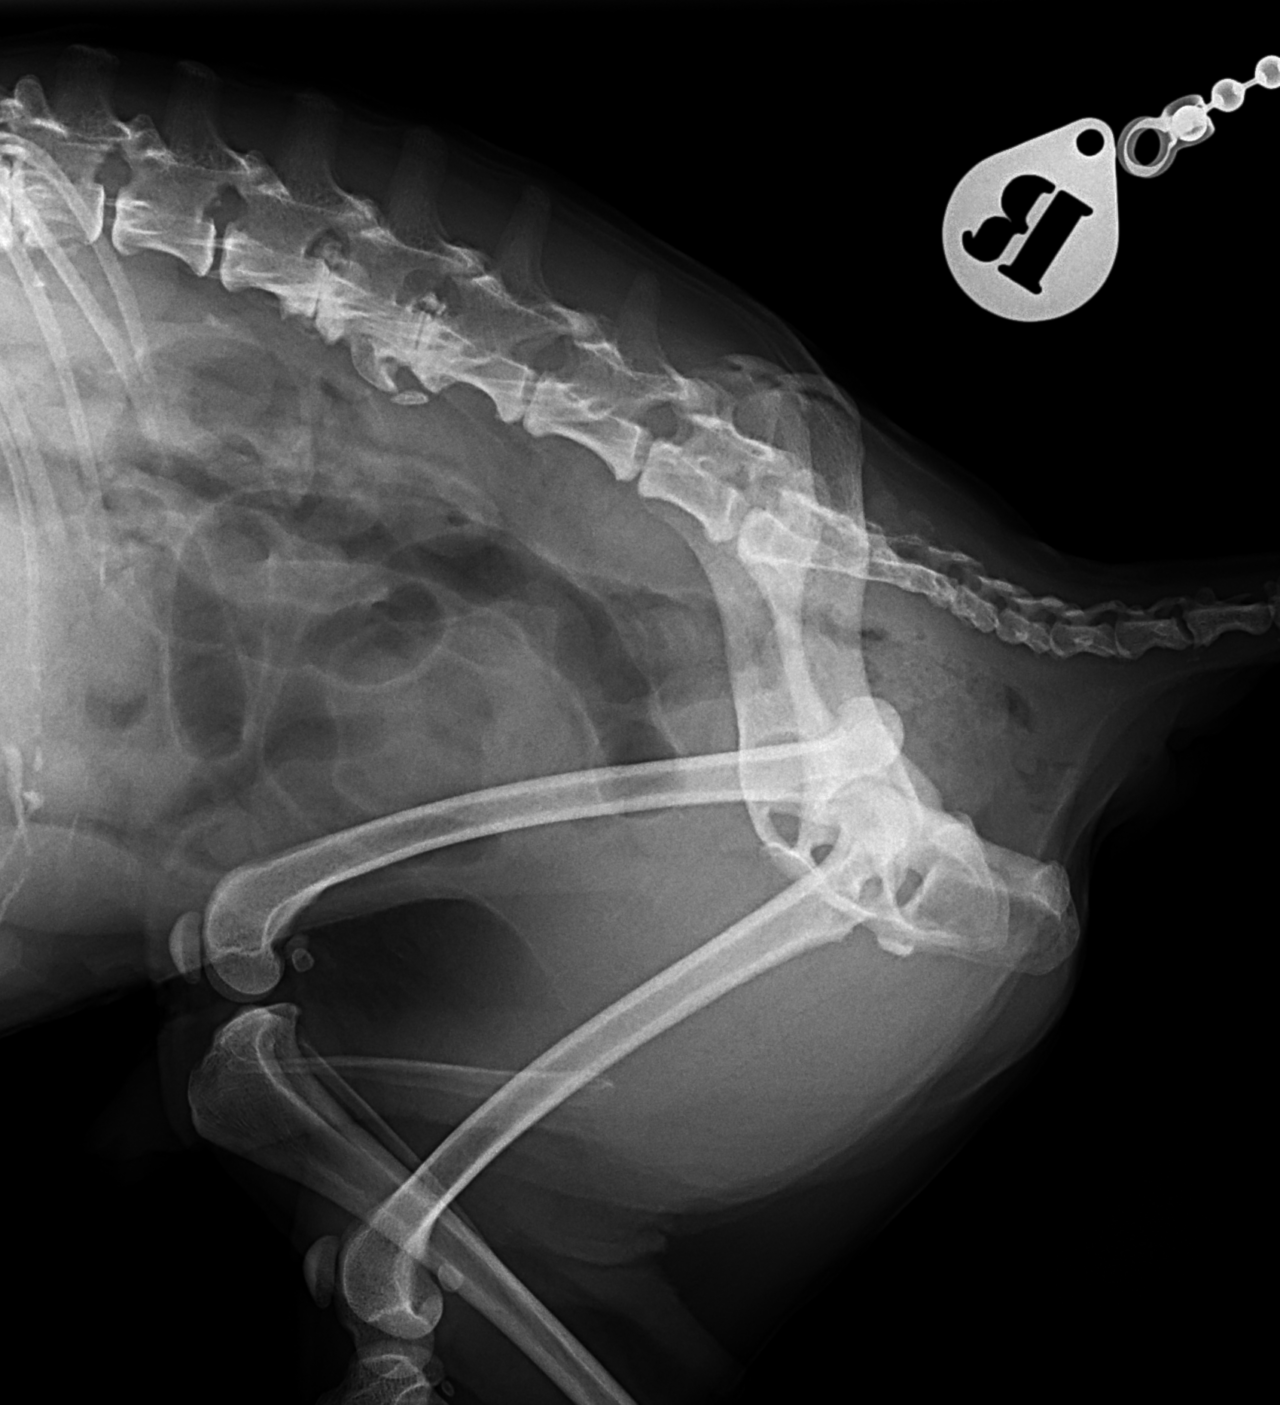

16歳のToy poodleさんが右の股関節を脱臼(背側前方)したとの事で主治医の先生から連絡がありました。1.9 Toggleとタイクロン(USP2)で整復術を実施しました。高齢ながら頑張ってくれました。2週間の安静期間が必要です。